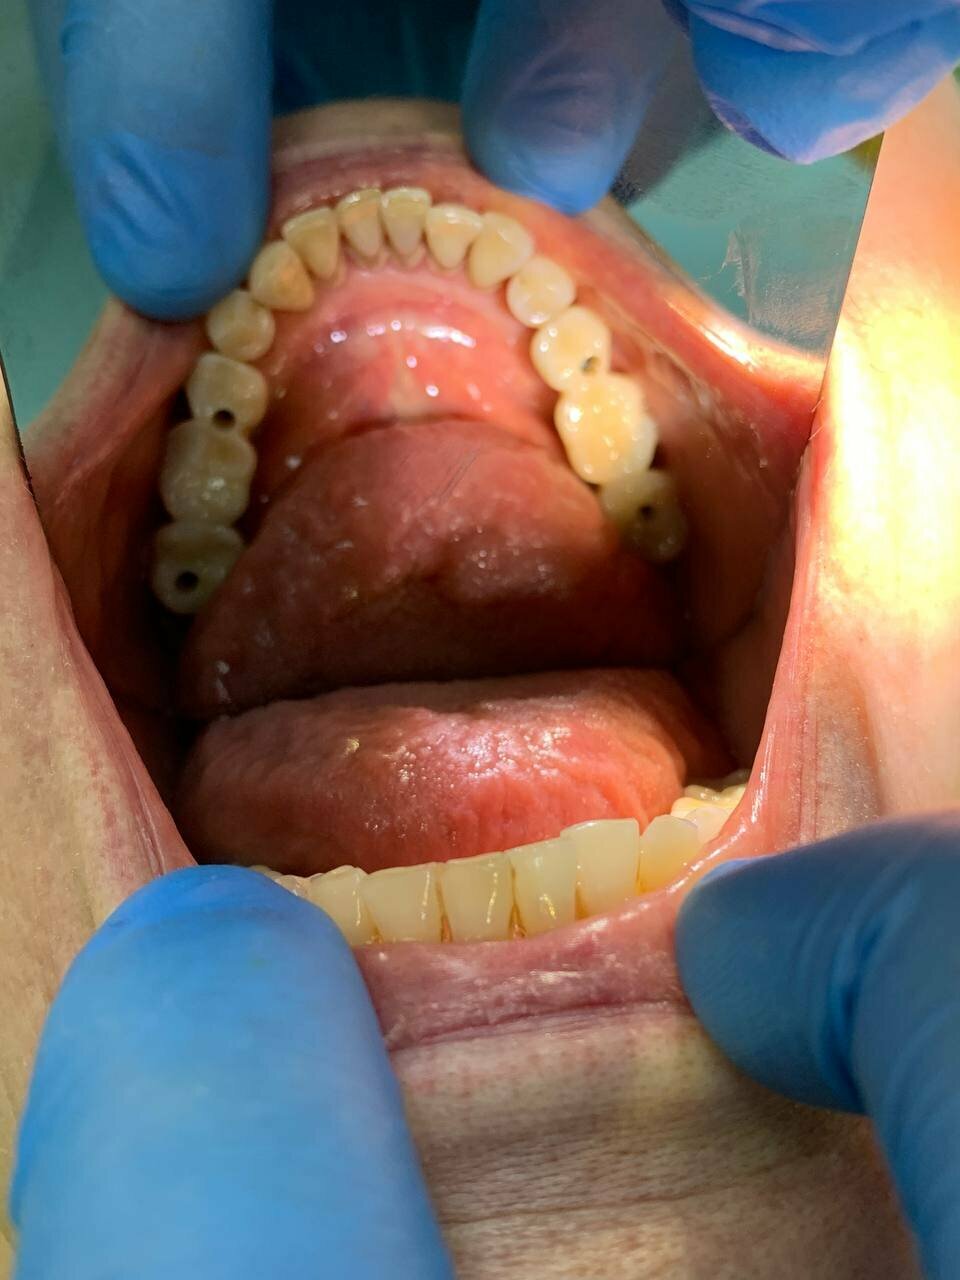

«Сити Дент» охватывает все основные направления стоматологии, включая общую стоматологию, ортодонтию, хирургию, эстетическую и детскую стоматологию. В клинике применяются современные технологии, такие как цифровая стоматология CAD/CAM, лечение под микроскопом, компьютерная томография и рентгенография. Среди дополнительных услуг — имплантология, костная пластика, гнатология, элайнеры, виниры, люминиры, отбеливание, протезирование и челюстно-лицевая хирургия.

Все на высшем уровне, ходили не первый раз и будем продолжать ходить. В первую очередь я обращаю внимание на отношение к человеку, специалисты стоматологии все рассказывают, показывают, объясняют и проводят все необходимые процедуры. В клинике я был на имплантации, со мной контактировали многие доктора, все понравились, работать с ними — просто песня! Команда очень сплоченная!